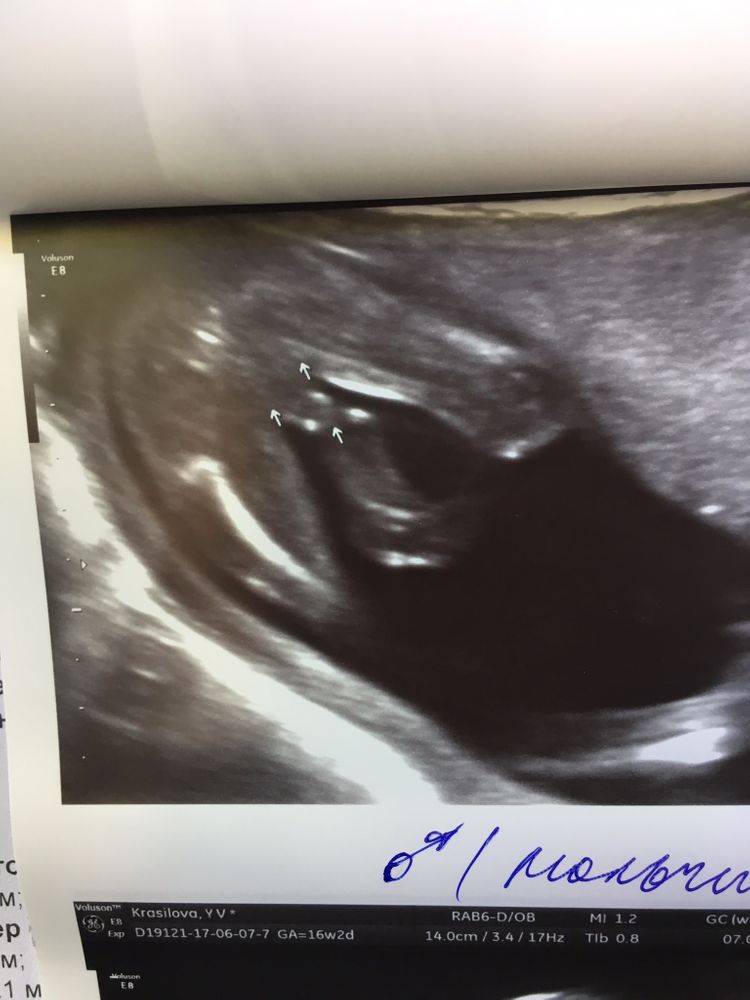

Как выглядели ваши девчонки на узи в 16-20 недель?

УЗИ, КТГ, доплерС мульчами там все ясно и понятно, а вот девчонки… полны загадок 😅

Если кому не сложно, покидайте ваши узи, где видно или подозревали девочку и она подтвердилась 🙏🏻 Заранее спасибо и лучи добра вам, девушки ❤️